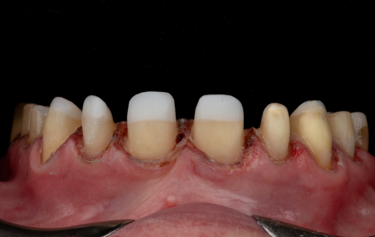

Figure 12: Provisional tooth preparations

Given the patient’s reduced dental arch, high strength of the final restorations would be an essential property to support the mechanics of her masticatory function. Ivoclar IPS e.max ZirCAD Prime Esthetic was chosen as the restorative material as it has a considerably higher compressive strength over IPS e.max. In addition, the shade graduation technology gives the restorations more translucency toward the incisal edges and allows them to achieve the necessary natural colouring of real teeth that’s’ so vital in an aesthetic rehabilitation[13]. Bone-sounding was completed, and there was ample sulcus depth to allow removal of approximately 1-1.5mm from the unattached gingiva, still leaving approximately 2mm sulcus depth. Using a digitally printed guide based on the provisional digital mock-up, a diode-laser was used to gentle re-contour the gingiva to give better symmetry for the planned final restorations (Fig. 10). The teeth were then prepared to respect the minimum manufacture tolerance of Zirconia restorations, whilst keeping the preparation into the natural teeth as minimal as possible following the Gürel reduction technique[14]. This technique helps safeguard that only the necessary tooth-surface is sacrificed during crown or veneer preparation, and ensures that the correct thickness of reduction for the planned restorative medium is achieved. Depth grooves of 0.8mm were cut mid-facially and 1.5mm reductions incisally, and the teeth then prepared for full coverage restorations respecting these grooves as the maximum tooth reduction level (Fig. 11).

The initial preparations (Fig. 12) were scanned and then temporised with bis-acryl temporary medium. This trial smile was assessed by the patient for a few weeks so that they were able to get used to the new OVD, slight modifications to tooth size and shape, and for them to assess the aesthetics and phonetics. During this time, the scans of the now prepared upper and lower arches were converted via the Exocad software so that milled temporary crowns could be manufactured using Ivoclar Telio CAD in shade B1. On the 2-week review visit the interim temporary restorations were removed and the newly-made milled restorations placed. The function was assessed, and slight occlusal adjustment made until the bite was balanced. The temporaries were then scanned again so the laboratory was aware of the slight modifications to the shape occlusally.

A 6-week period was allowed to pass to give the gingiva time to heal and settle around the milled temporary restorations. On review the patient was very happy with the aesthetics of her smile but wanted the teeth a little whiter in colour. The form and function of the teeth was balanced, and the patient was comfortable at the new OVD. The temporary restorations were easily removed, followed by final refinement of the tooth preparations, and then retraction with PTFE placed into the sulcus ahead of a Trios intra-oral digital scan of the final preparations (Fig. 13). The posterior bite relationship of the prepared teeth was digitally recorded over the premolar area by using the anterior upper and lower 4 crowns to support the patient in the correct centric relation position.